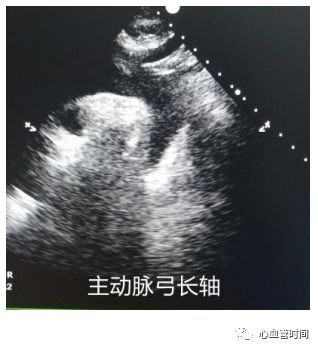

主动脉弓长轴切面

主要观察主动脉有无增宽、缩窄、异常回声。对于左室壁肥厚又不能明确病因的一定要注意有无

主动脉缩窄。

主要观察主动脉有无增宽、缩窄、异常回声。对于左室壁肥厚又不能明确病因的一定要注意有无

主动脉缩窄。